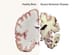

'Z' Drugs Significantly Boost Fracture Risk in Dementia Patients

CHICAGO — Prescribing hypnotics such as zolpidem (multiple brands), zopiclon (Lunesta, Sunovion), or zaleplon (Sonata, Pfizer) to treat sleep problems in dementia patients significantly increases fracture risk in this vulnerable population, new research shows.

About 60% of people with dementia experience sleep disturbances, which can include insomnia and excessive daytime sleeping, Maidment said at a press briefing here.